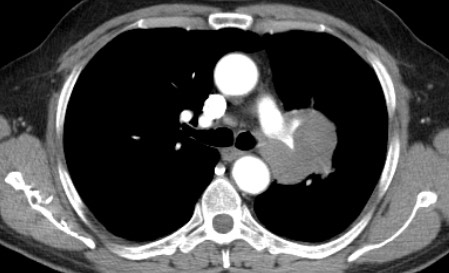

2859. Анализируя представленные снимки, можно предположить вовлечение в процесс